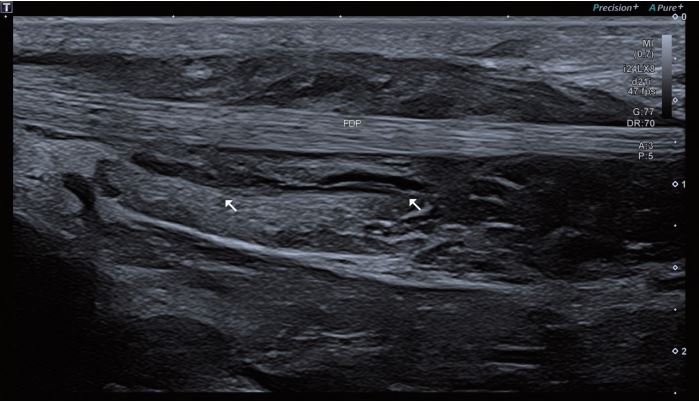

Зображення 1 Сухожилля FDP у поздовжній площині.

Чітко видно зміни ехогенності прилеглого м'яза.